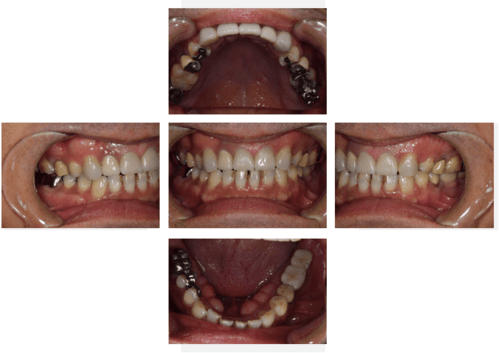

インプラント治療の症例5

レントゲン写真

- Before

- After

口腔内写真

- 途中経過

| 年齢 | 60代・女性 |

|---|---|

| 主訴 | 左下6番、7番 歯ぐきの腫れが気になり来院。 歯周病がかなり進行しており骨がほとんどない状態で動揺もあった。 |

| 治療内容 | インプラント治療 動揺がひどく歯を残すことが難しいため抜歯へ。 その後骨造成を行いインプラントを埋入。 |

| 治療費 | 合計:1,683,000円 内訳 診断料:55,000円 埋入料:165,000円×2本 チタンメッシュ:55,000円×2本 GBR:110,000円×2本 サージカルガイド:66,000円 静脈内鎮静麻酔:77,000円×2回 2次オペ:22,000円×2本 仮歯:55,000円×2本 上部構造(フルジルコニア):187,000円×2本 APF(歯肉弁根尖側移動術):110,000円×2本 (2024年1月現在) |

| 治療期間 | 16ヶ月 |

| リスク・副作用 | インプラントはご自身のセルフケアに加え、歯科医院でのメインテナンスが不十分だと、歯周病になることがある。 歯ぎしり、食いしばりが強い方はインプラントの上部構造が割れてしまうことがあるため、就寝時にマウスピースの使用が必要。 |

| 治療方針 | 歯周病がかなり進行していて骨吸収がみられるのでチタンメッシュと骨補填材を使った骨造成が必要。 先に骨造成を行い骨が再生されるのを待って埋入手術を行う。 歯ブラシがしやすくなるようにAPF ( 歯肉弁根尖側移動術 )も行う。 |

| 特記事項 | 今回は印象材ではなく光学スキャナーを使用して型どりを行った。 |

| 担当者所見 | 骨が再生するか難しいところだったが無事埋入でき問題なく結合できた。 また今回は印象材ではなく光学スキャナーを使用して印象したため患者さまの負担がかなり軽減されたと思う。 上部構造セット後しっかりとかめている。 今後も定期的にメインテナンスしていく。 |